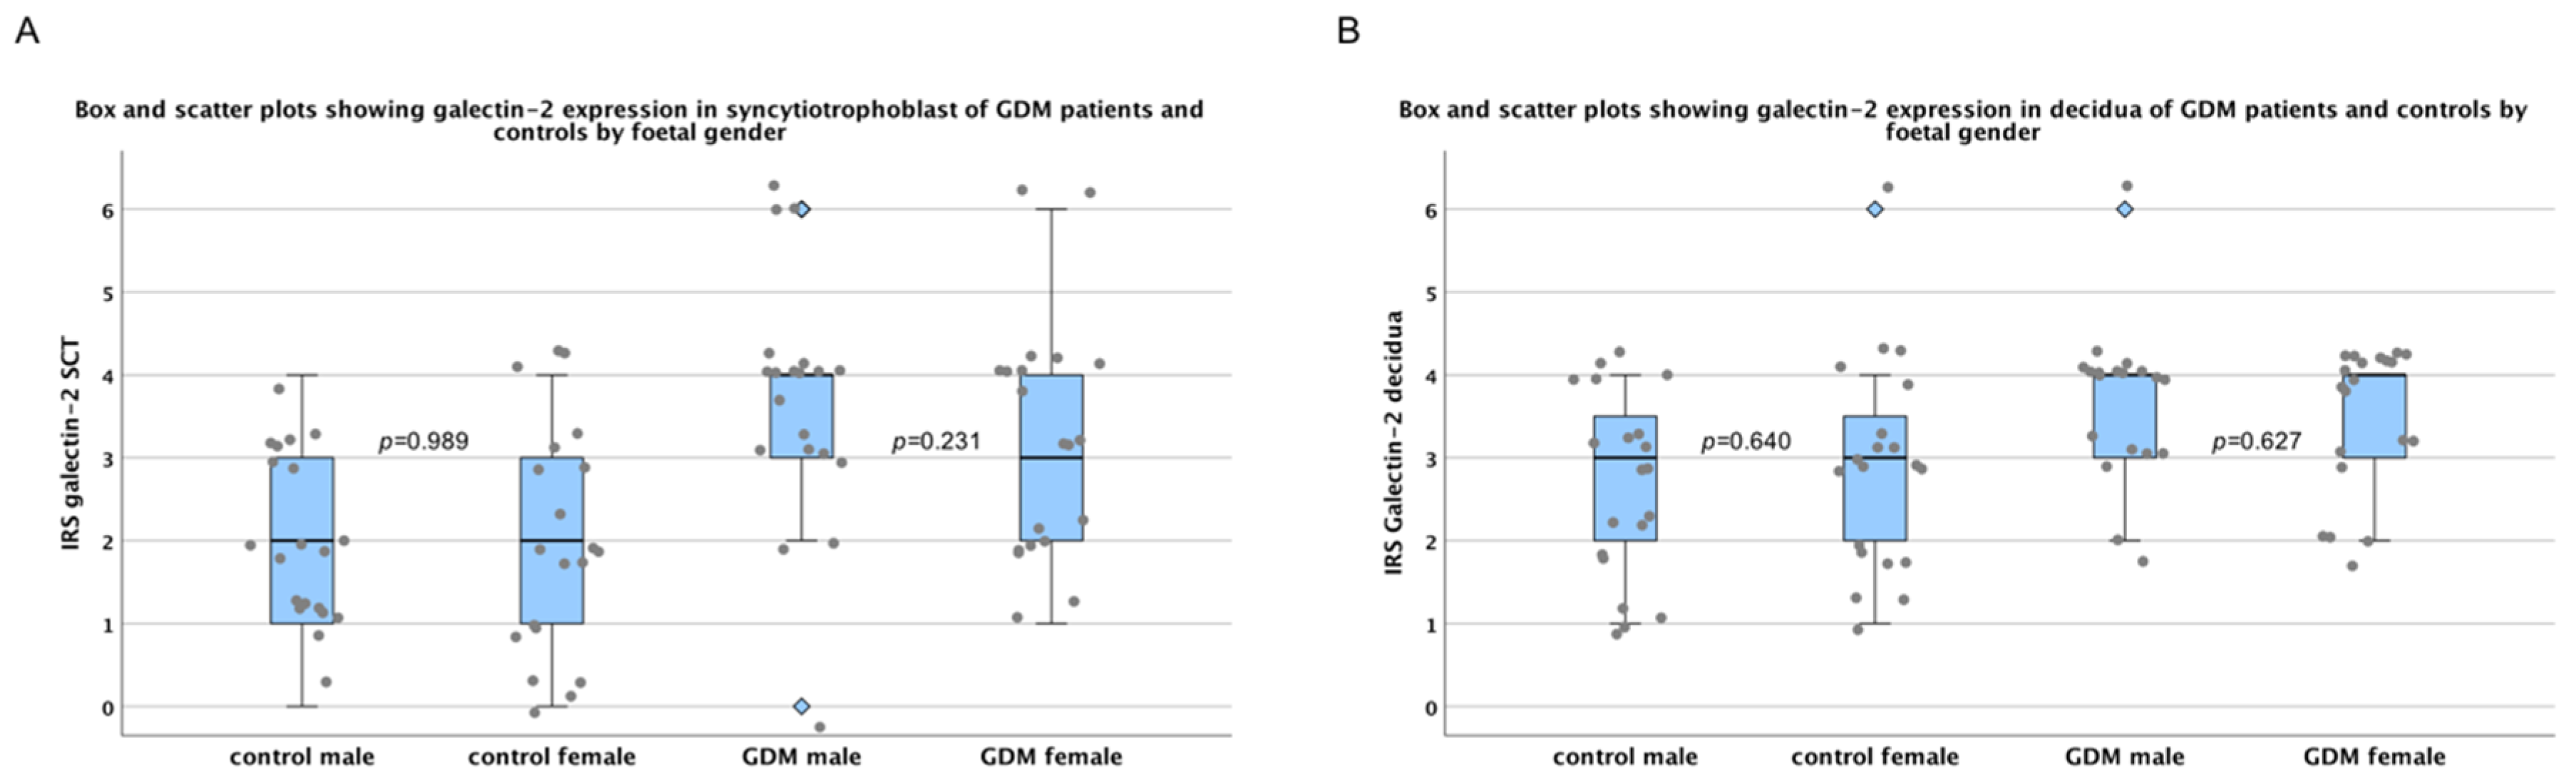

2.1. There Are No Sex-Specific Differences in Galectin-2 Expression